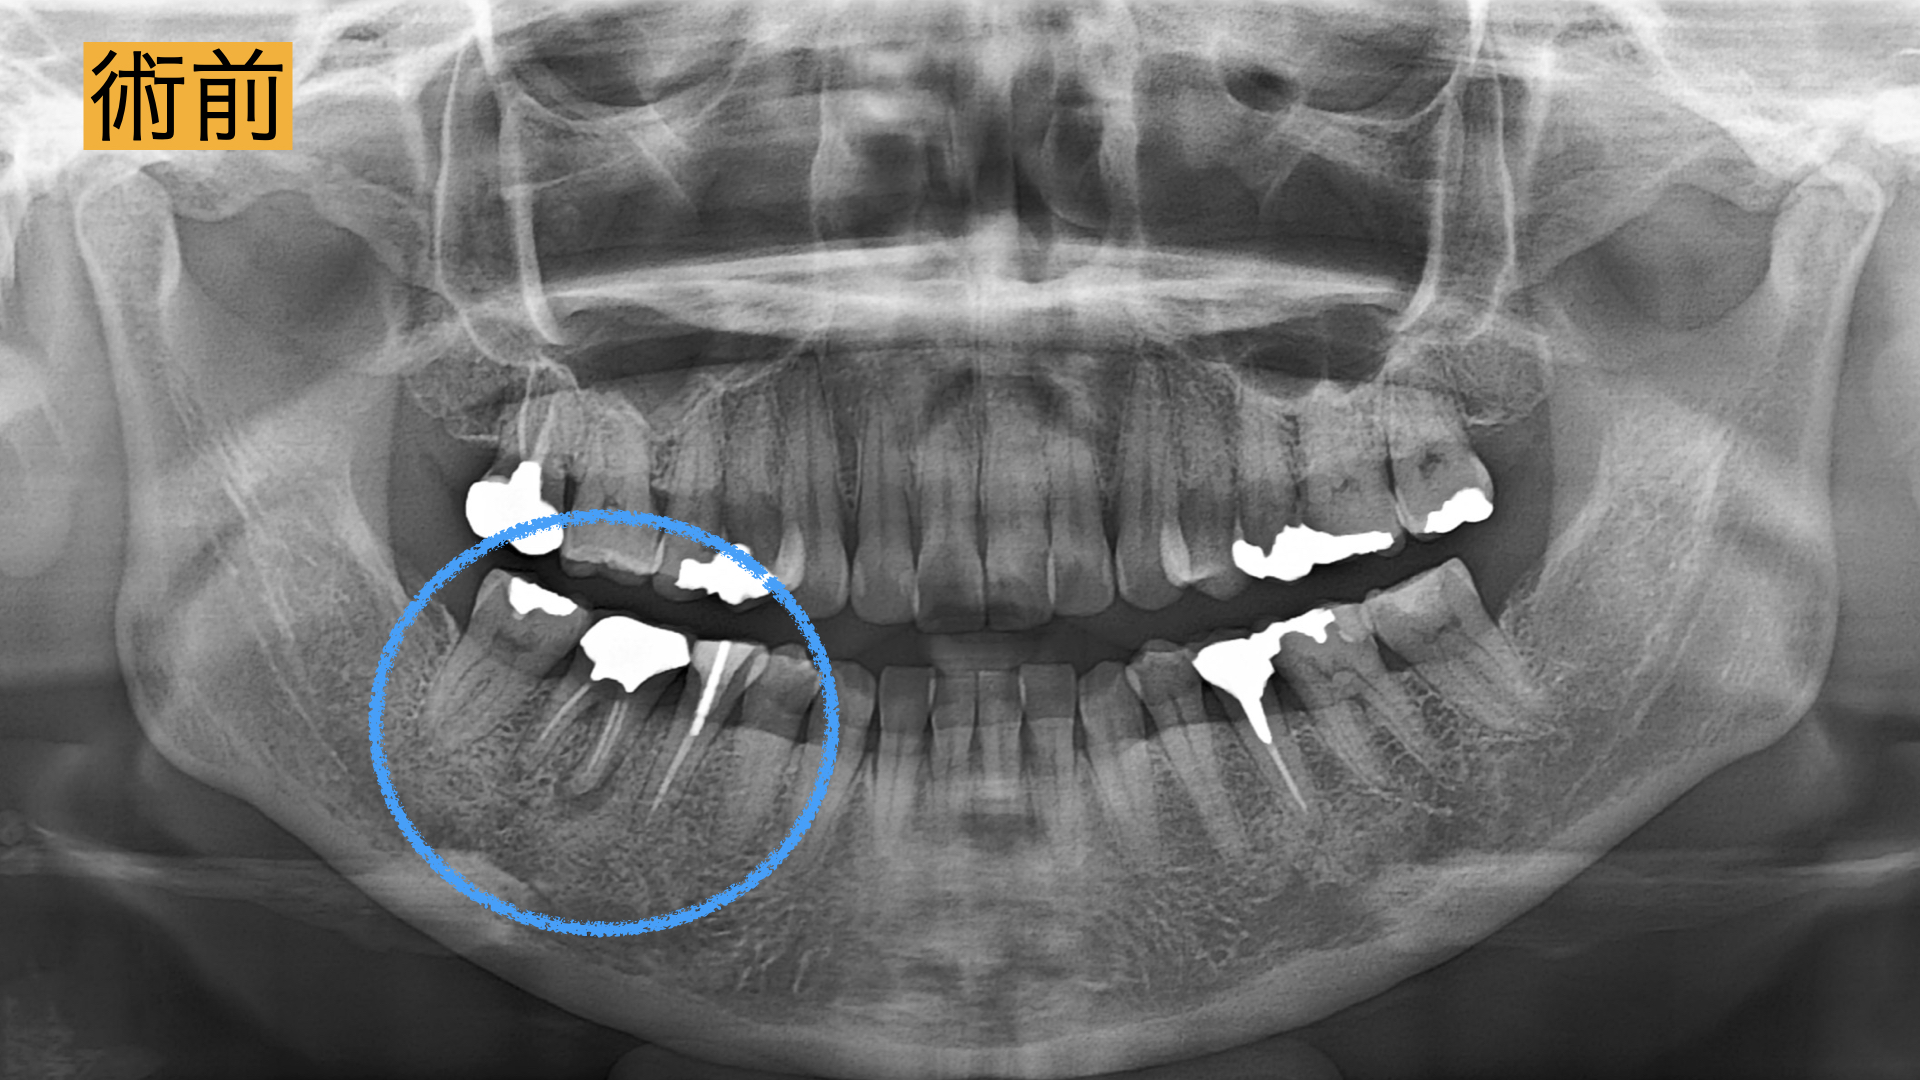

右下の10年前に治療した歯の歯茎が腫れた、歯磨きすると血が出る。3年前に検診した歯科医院で数年後腫れる可能性があると言われた。日によって歯茎に白いできものができる。できものを潰すと1週間くらい良くなる。 最近、口臭も気になるので治せるのならば治療したい。

今回、根の治療が3回目とのこともあったため被せ物・土台を外して長期的予後が見込める場合は精密根管治療、見込めない場合は抜歯してブリッジ治療。と決定いたしました。

術後

術直後から痛み、腫れは、解消し2年間の経過観察も問題なく過ごせましたとのことでした。 レントゲンで骨の回復が確認とれ、非常に驚かれておりました。